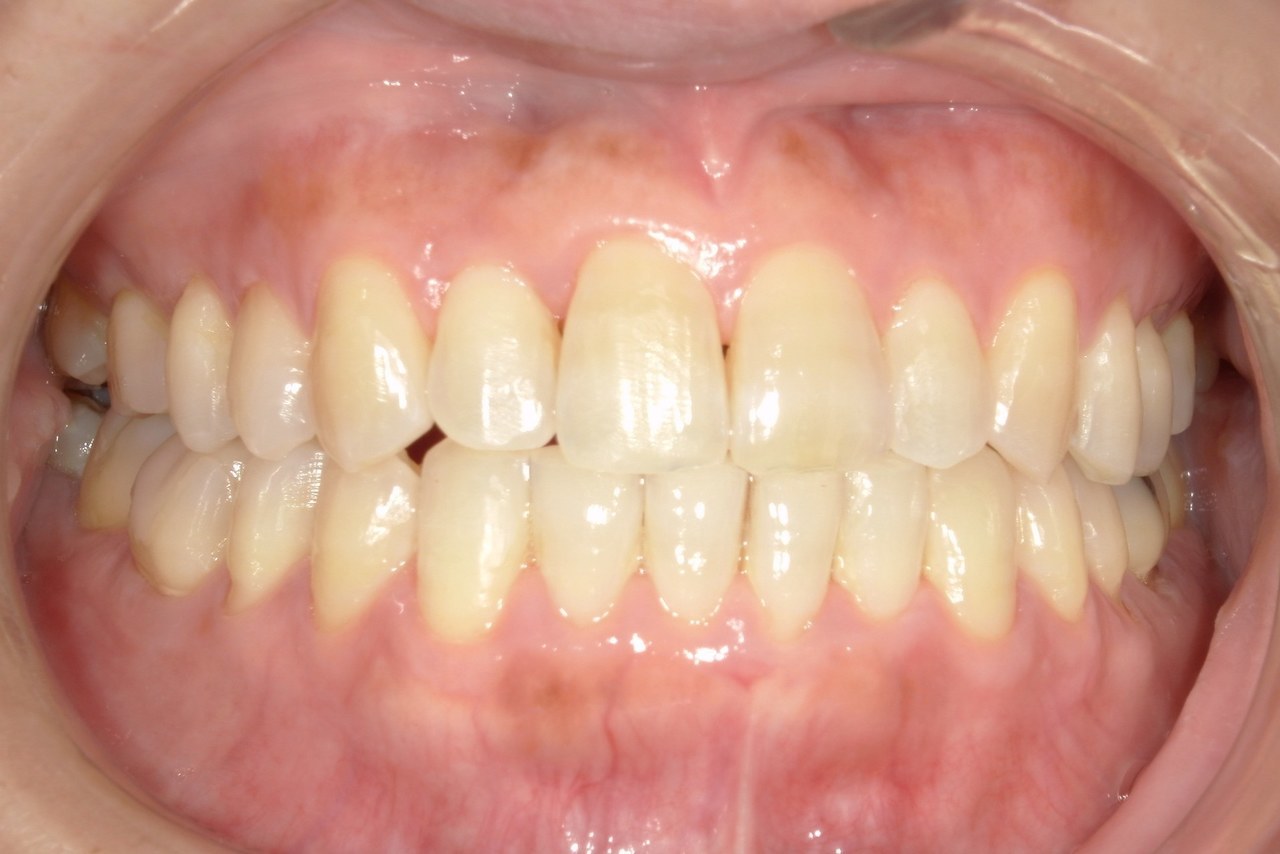

After

浜松市中央区・自動車学校前駅のインビザラインの症例

N.T 20代女性

上の前歯が出ているのが気になる、左下の第二小臼歯が内側に入っているのが気になるとの主訴でご来院。

上の前歯を下げて左下の第二小臼歯を外に移動させることで気になっていた上顎前突を改善しました。

治療の期間:R4. 4/22〜R6. 11/2

治療の価格:66万円